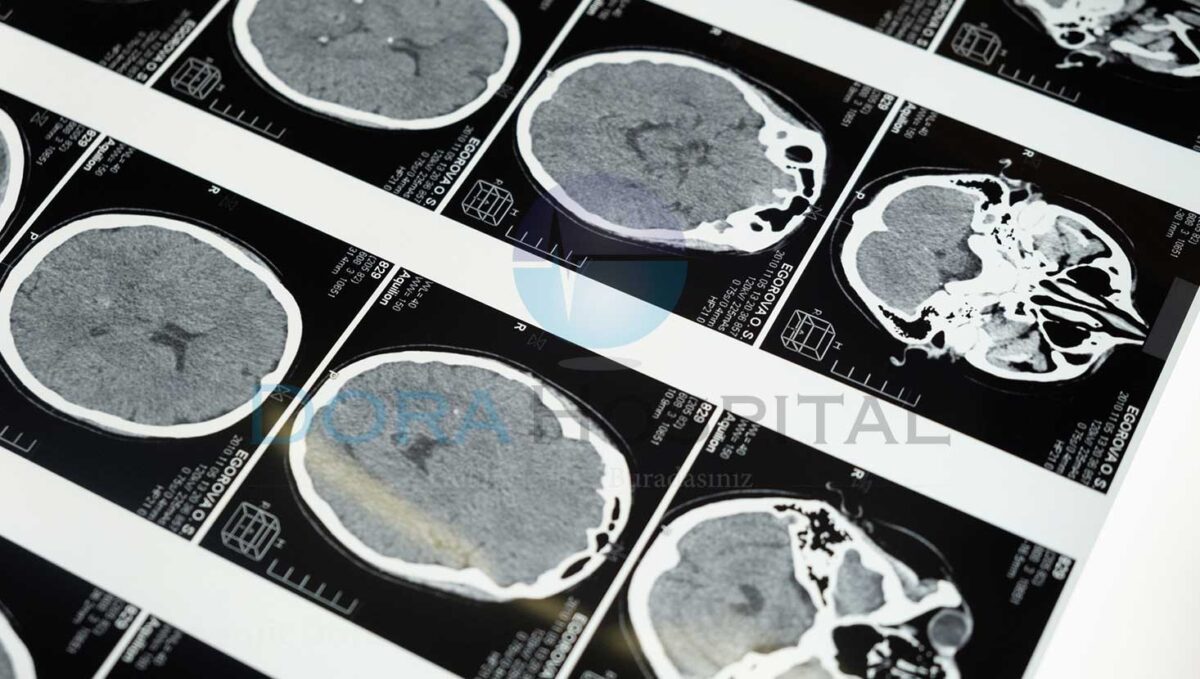

Tanı koyma konusunda özellikle uygulanan metot fiziki muayene şekli olarak bilinmektedir. Bunun dışında kan testi yapılmaktadır. Kan testi sayesinde vücuda bulaşmış olan menenjit rahatsızlığının ne türde olup olmadığına bakılmaktadır. Gerekli görüldüğü vakit hekim kararı ile BT yani bilgisayarlı tomografi çekilmektedir. Böylece tam anlamıyla menenjit tanısı konulabilmektedir. Bu işlemler dışında lomber ponksiyon adı verilen tanı koyma işlemi menenjit konusunda önemli yer tutmaktadır.